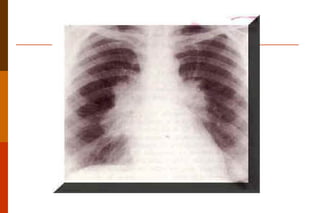

Tuberculose doença causada pelo  Mycobacterium tuberculosis,  cuja manifestação clínica depende da resposta imunitária do organismo hospedeiro. Pode se primária, secundária ou miliar. A tuberculose primária é a que ocorre em indivíduos que têm o primeiro contato com o  M. tuberculosis , e determina diversas reações: exsudativa  (nódulo exsudativo),  produtiva   (granuloma duro),  produtivo caseoso  (granuloma com necrose caseosa) e  cicatrizada  (nódulo de Ghon).

Tuberculose Ao conjunto do nódulo de Ghon, linfangite e linfadenite dá-se o nome de complexo primário ou de Ghon.  A tuberculose secundária pode manifestar-se sob três formas macroscópicas: apical,  ácino-nodosa miliar.

Tuberculose doença causadapelo Mycobacterium tuberculosis, cuja manifestação clínica depende da resposta imunitária do organismo hospedeiro. Pode se primária, secundária ou miliar. A tuberculose primária é a que ocorre em indivíduos que têm o primeiro contato com o M. tuberculosis , e determina diversas reações: exsudativa (nódulo exsudativo), produtiva (granuloma duro), produtivo caseoso (granuloma com necrose caseosa) e cicatrizada (nódulo de Ghon).

Tuberculose Ao conjuntodo nódulo de Ghon, linfangite e linfadenite dá-se o nome de complexo primário ou de Ghon. A tuberculose secundária pode manifestar-se sob três formas macroscópicas: apical, ácino-nodosa miliar.